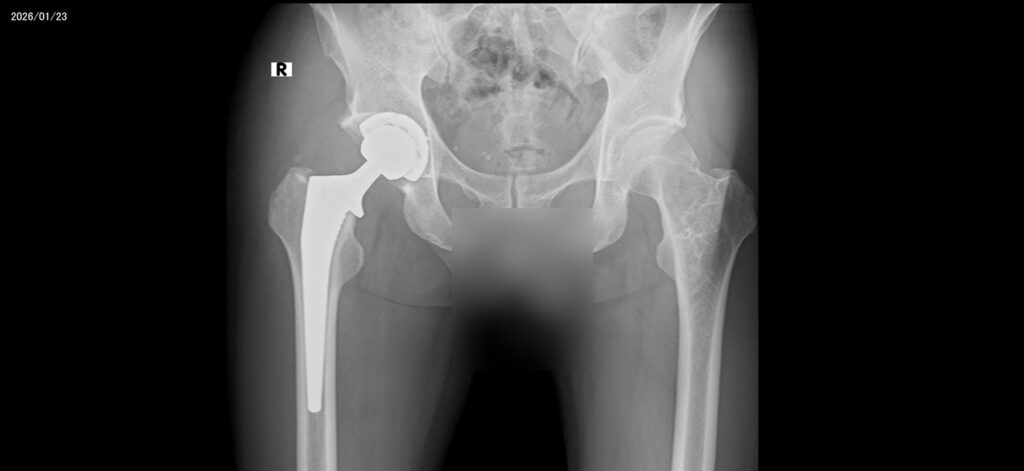

右変形性股関節症(人工関節置換術)

今日は一日忙しかった。リハビリ3回。シャワー。レントゲン。を行った。本日から独歩のリハビリが始まり、入院して初めて病院の周りだが外を歩きました。気持ちよかった。階段の登り降りも普通にできて良い感じであった。ただし水飲みすぎのせいか、リハビリの途中でもトイレに行かせてもらった。困ったものだ〜本日退院の日程が決まった。1月26日(月)10:00だ〜嬉しい。